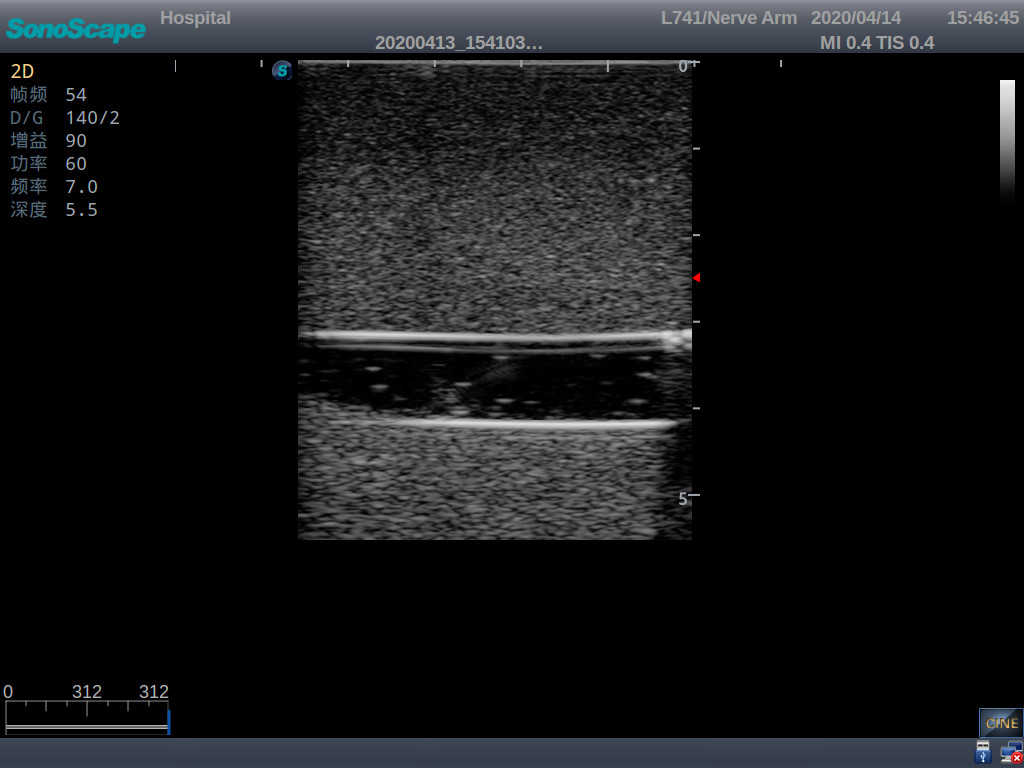

Model TYE1510.1

1)   Made of high molecular polymer ultrasound material, close to the real skin

2)   It can be used by real ultrasound machines

3)   Clear and real images of the tissues and organs (basilic vein and superior vena cava)